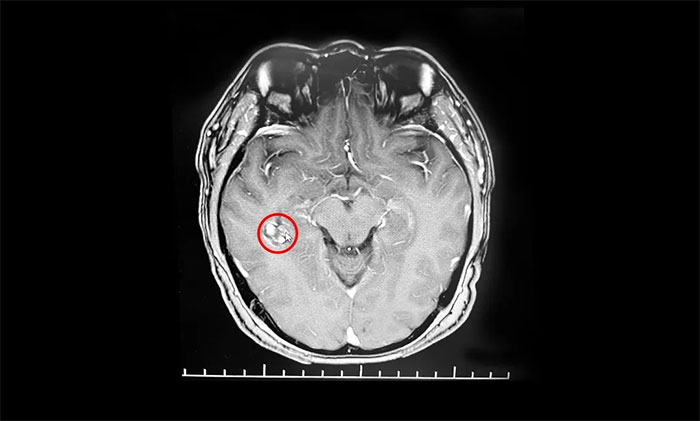

入院后,行海馬MRI平掃+MRS+MRSI檢查,MRS提示右側(cè)海馬Cho峰升高;掃及右側(cè)顳葉深部(側(cè)腦室顳角外下部)見一直徑約15mm類圓形異常信號(hào);右側(cè)側(cè)腦室顳角稍寬;颊呒韧哐獕翰∈4年,曾因右側(cè)顳部海綿狀血管瘤致蛛網(wǎng)膜下腔出血2次。楊忠旭教授結(jié)合患者癥狀,病史,磁共振、腦電圖等系列檢查,考慮海綿狀血管瘤及周圍皮層為致癲灶;颊咭呀(jīng)明確有反復(fù)出血史,手術(shù)指征明顯,需行手術(shù)切除治療,預(yù)防再次出血引起神經(jīng)功能及癲癇等癥狀。

▲ 海綿狀血管瘤